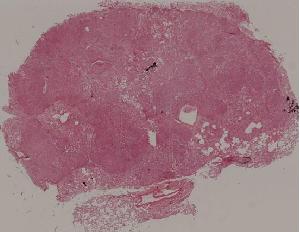

77. Chronic pyelonephritis